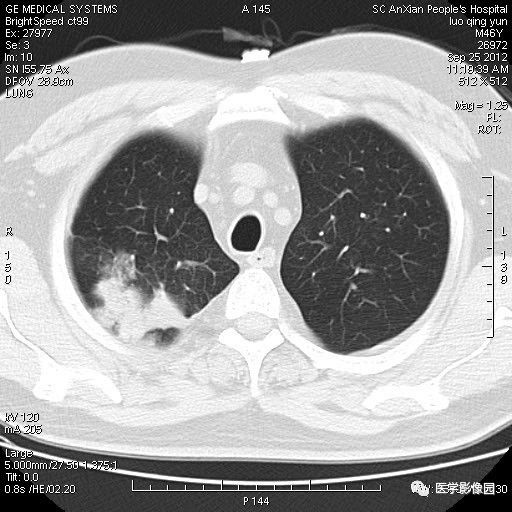

影像学表现:右上肺见不规则团块状高密度阴影,略有分叶级毛刺,边缘模糊,邻近胸膜增厚,增强扫描呈轻中度强化。

诊断结果:右上肺炎性假瘤

本病影像学表现无绝对特征性。单发多见,多位于肺表浅部位,多呈圆形或椭圆形,直径多在2-5cm或更大;多有假包膜,边缘多清晰光整,有时也毛糙,并可有分叶或毛刺;邻近胸膜局限性增厚、牵拉,病灶边缘呈桃尖样突起即桃尖征(尖端指向胸膜);增强扫描多呈中度均匀强化,持续时间较长。亦可显著强化。